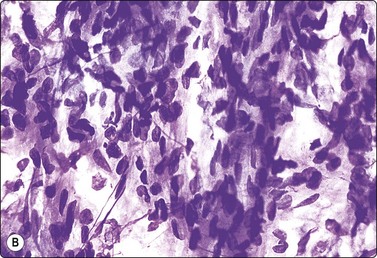

Sarcomatoid renal cell carcinoma is no longer distinguished as a subtype since this pattern can occur focally in any type of RCC. The tumor tissue is poorly differentiated of highly pleomorphic, anaplastic and often with spindle-shaped cells (see Fig. 12.21). This pattern, which resembles a pleomorphic sarcoma, is seen focally in 1.5% of RCC and suggests a poor prognosis.82,83

image

Fig. 12.21 Renal cell carcinoma, sarcomatoid type

Moderately cohesive, pleomorphic spindle cells with malignant nuclear features (A, MGG; B, H&E; HP); (C) Corresponding tissue section (H&E, IP).